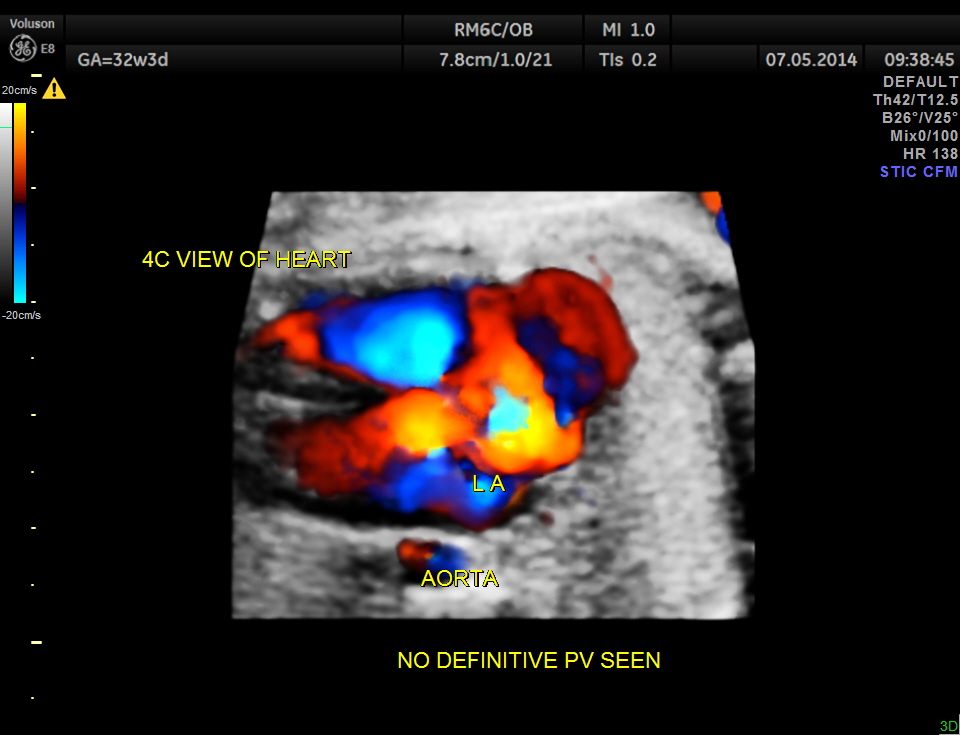

The following is a glass body imaging with a low flow setting. No pulmonary vein draining into LA could be made out.

A transverse vessel is seen below the left atrium and is not seen to drain into the left atrium.

No definitive pulmonary vein draining into the left atrium could be made out . A common transverse vessel was seen beneath the left atrium . The LA & RA were smaller than the RA. Similarly the Aorta and the aortic arch were smaller than the pulmonary artery and the ductal arch due to the increased flow in the right side.

So a probable diagnosis of Total Anomalous Pulmonary Venous Connection with severe symmetric fetal growth restriction was offered. The patient apparently went into a spontaneous abortion and no autopsy study was done. So there is no confirmation again.